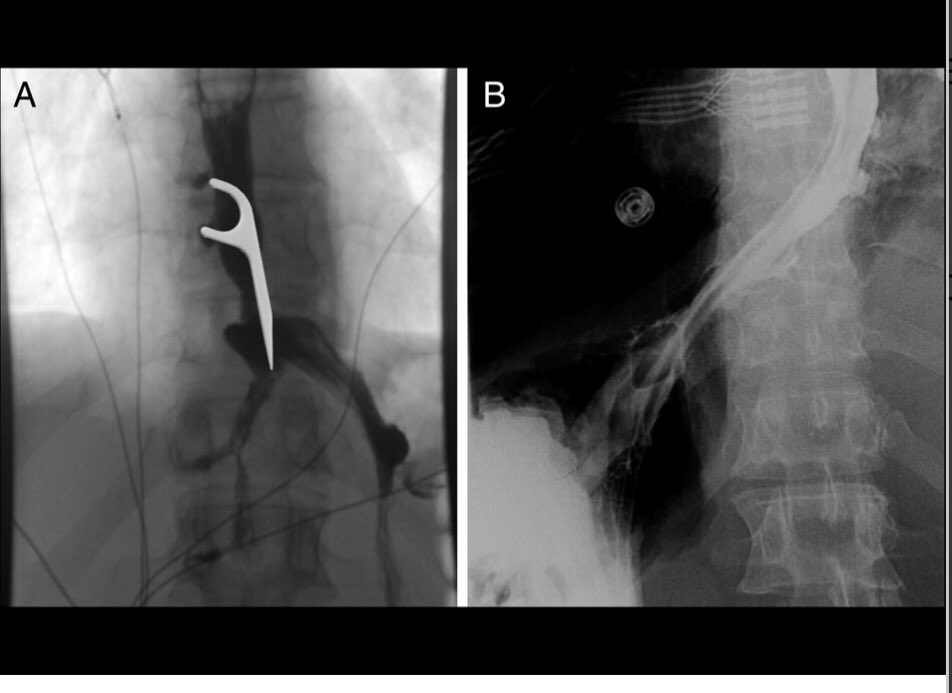

A great overview of polypectomy by Dr. Siddiqui from @UChicagoGI!

Key takeaways:

➡️ inspect and characterize every lesion

➡️ know your tools

➡️ avoid manipulation of polyps if referring out to AE

➡️ and don’t panic in case of adverse events!